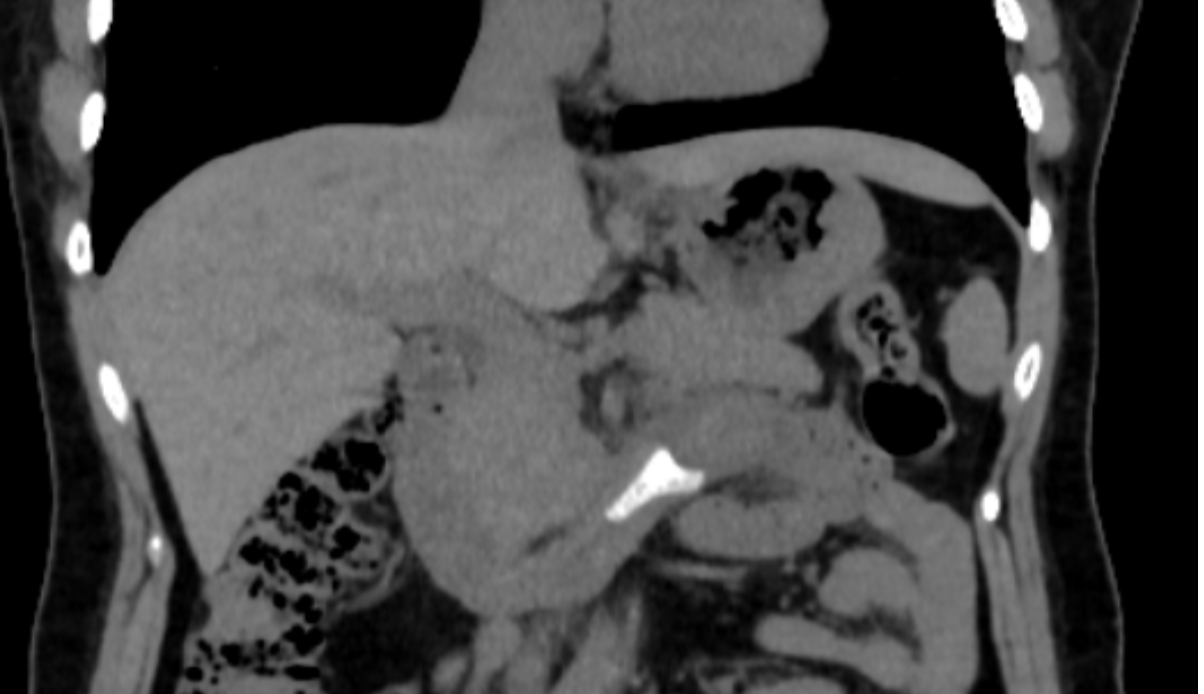

腹部CT提示患者消化道内存在异物。